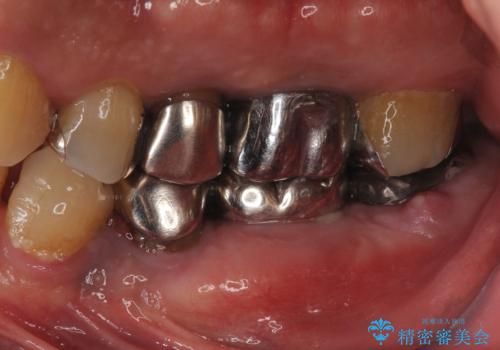

[40代男性・受け口] 下のみ抜歯の矯正治療

- 前歯の反対咬合を主訴に来院。

上の犬歯2本はすでに抜歯されており、隙間がありました。

歯の数を揃えて下の前歯を下げるため、下を二本抜歯して並べました。

40代男性ということもあり、なかなか下の臼歯が動かず隙間を閉じるのが大変でしたが、無事治療を終えることができました。

現在、すべての詰め物のやりかえを行っています。